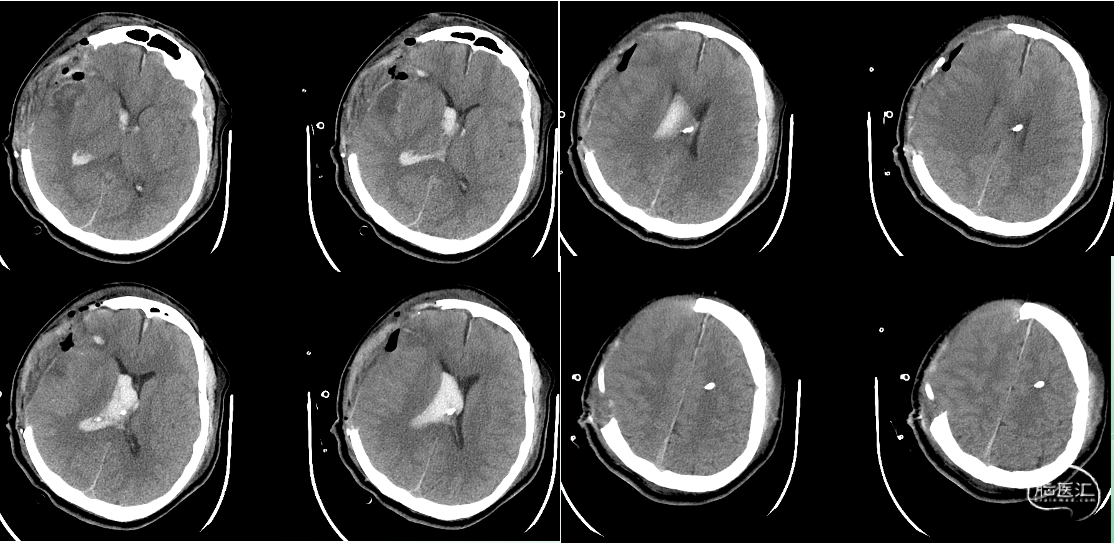

术后即时影像

出院时影像